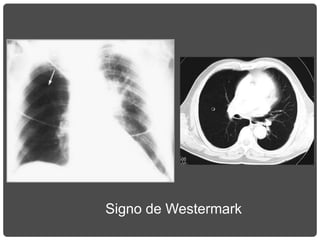

HIPERCLARIDAD UNILATERAL

Signo de Westermark

TEP

Signo de la

Joroba de Hampton

Focos de condensación

segmentarios de

localización periférica y

aspecto cuneiforme, los que

a veces presentan un borde

medial convexo y son de

base pleural. Estas sombras

representan áreas de infarto

o hemorragia pulmonar.